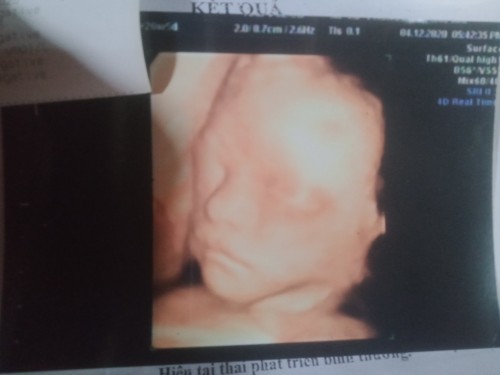

trong chuẩn nha mom, ko có nhỏ nha